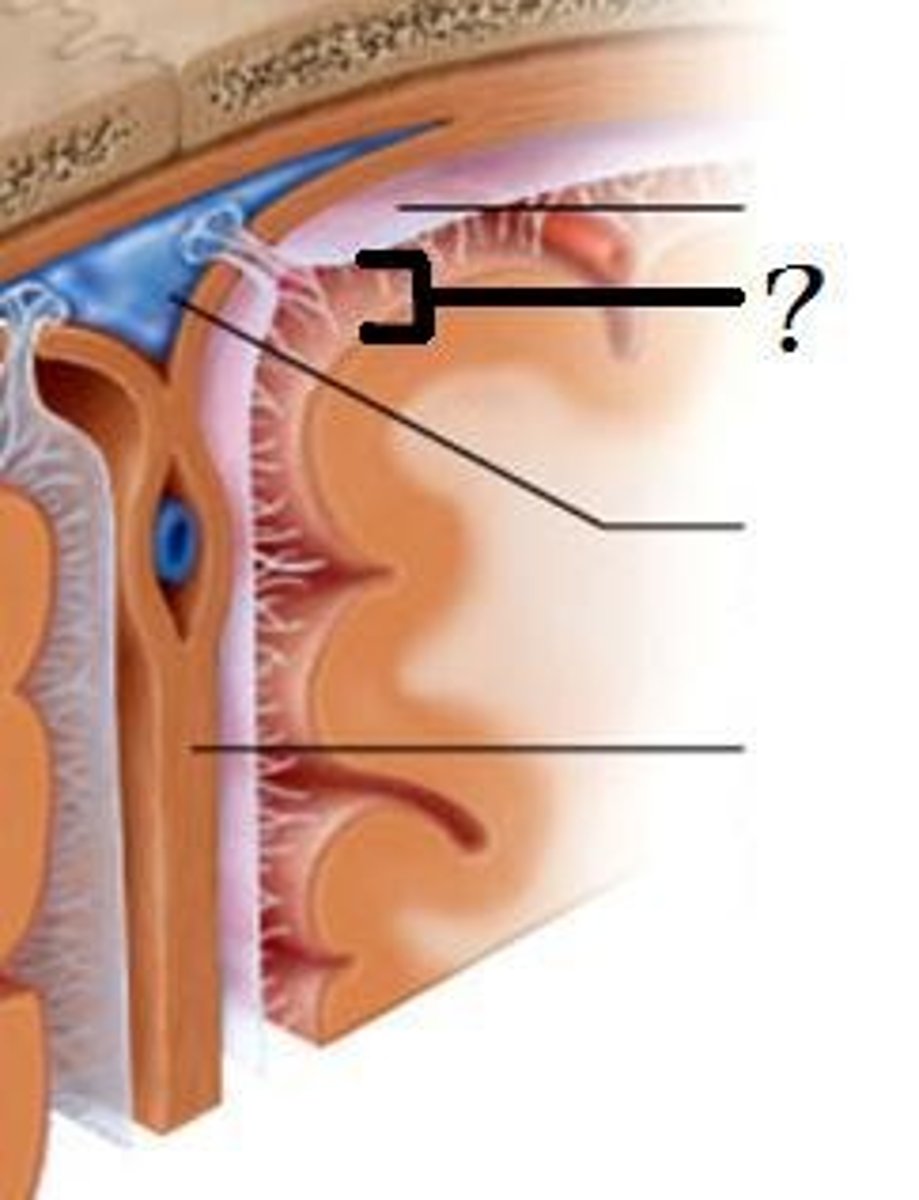

tentorium cerebelli

between cerebrum and cerebellum

falx cerebri